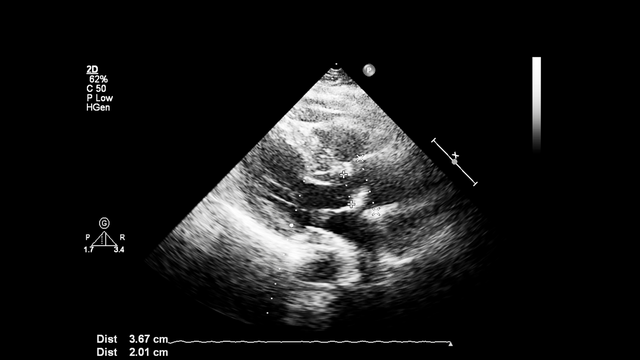

Chẩn đoán bệnh